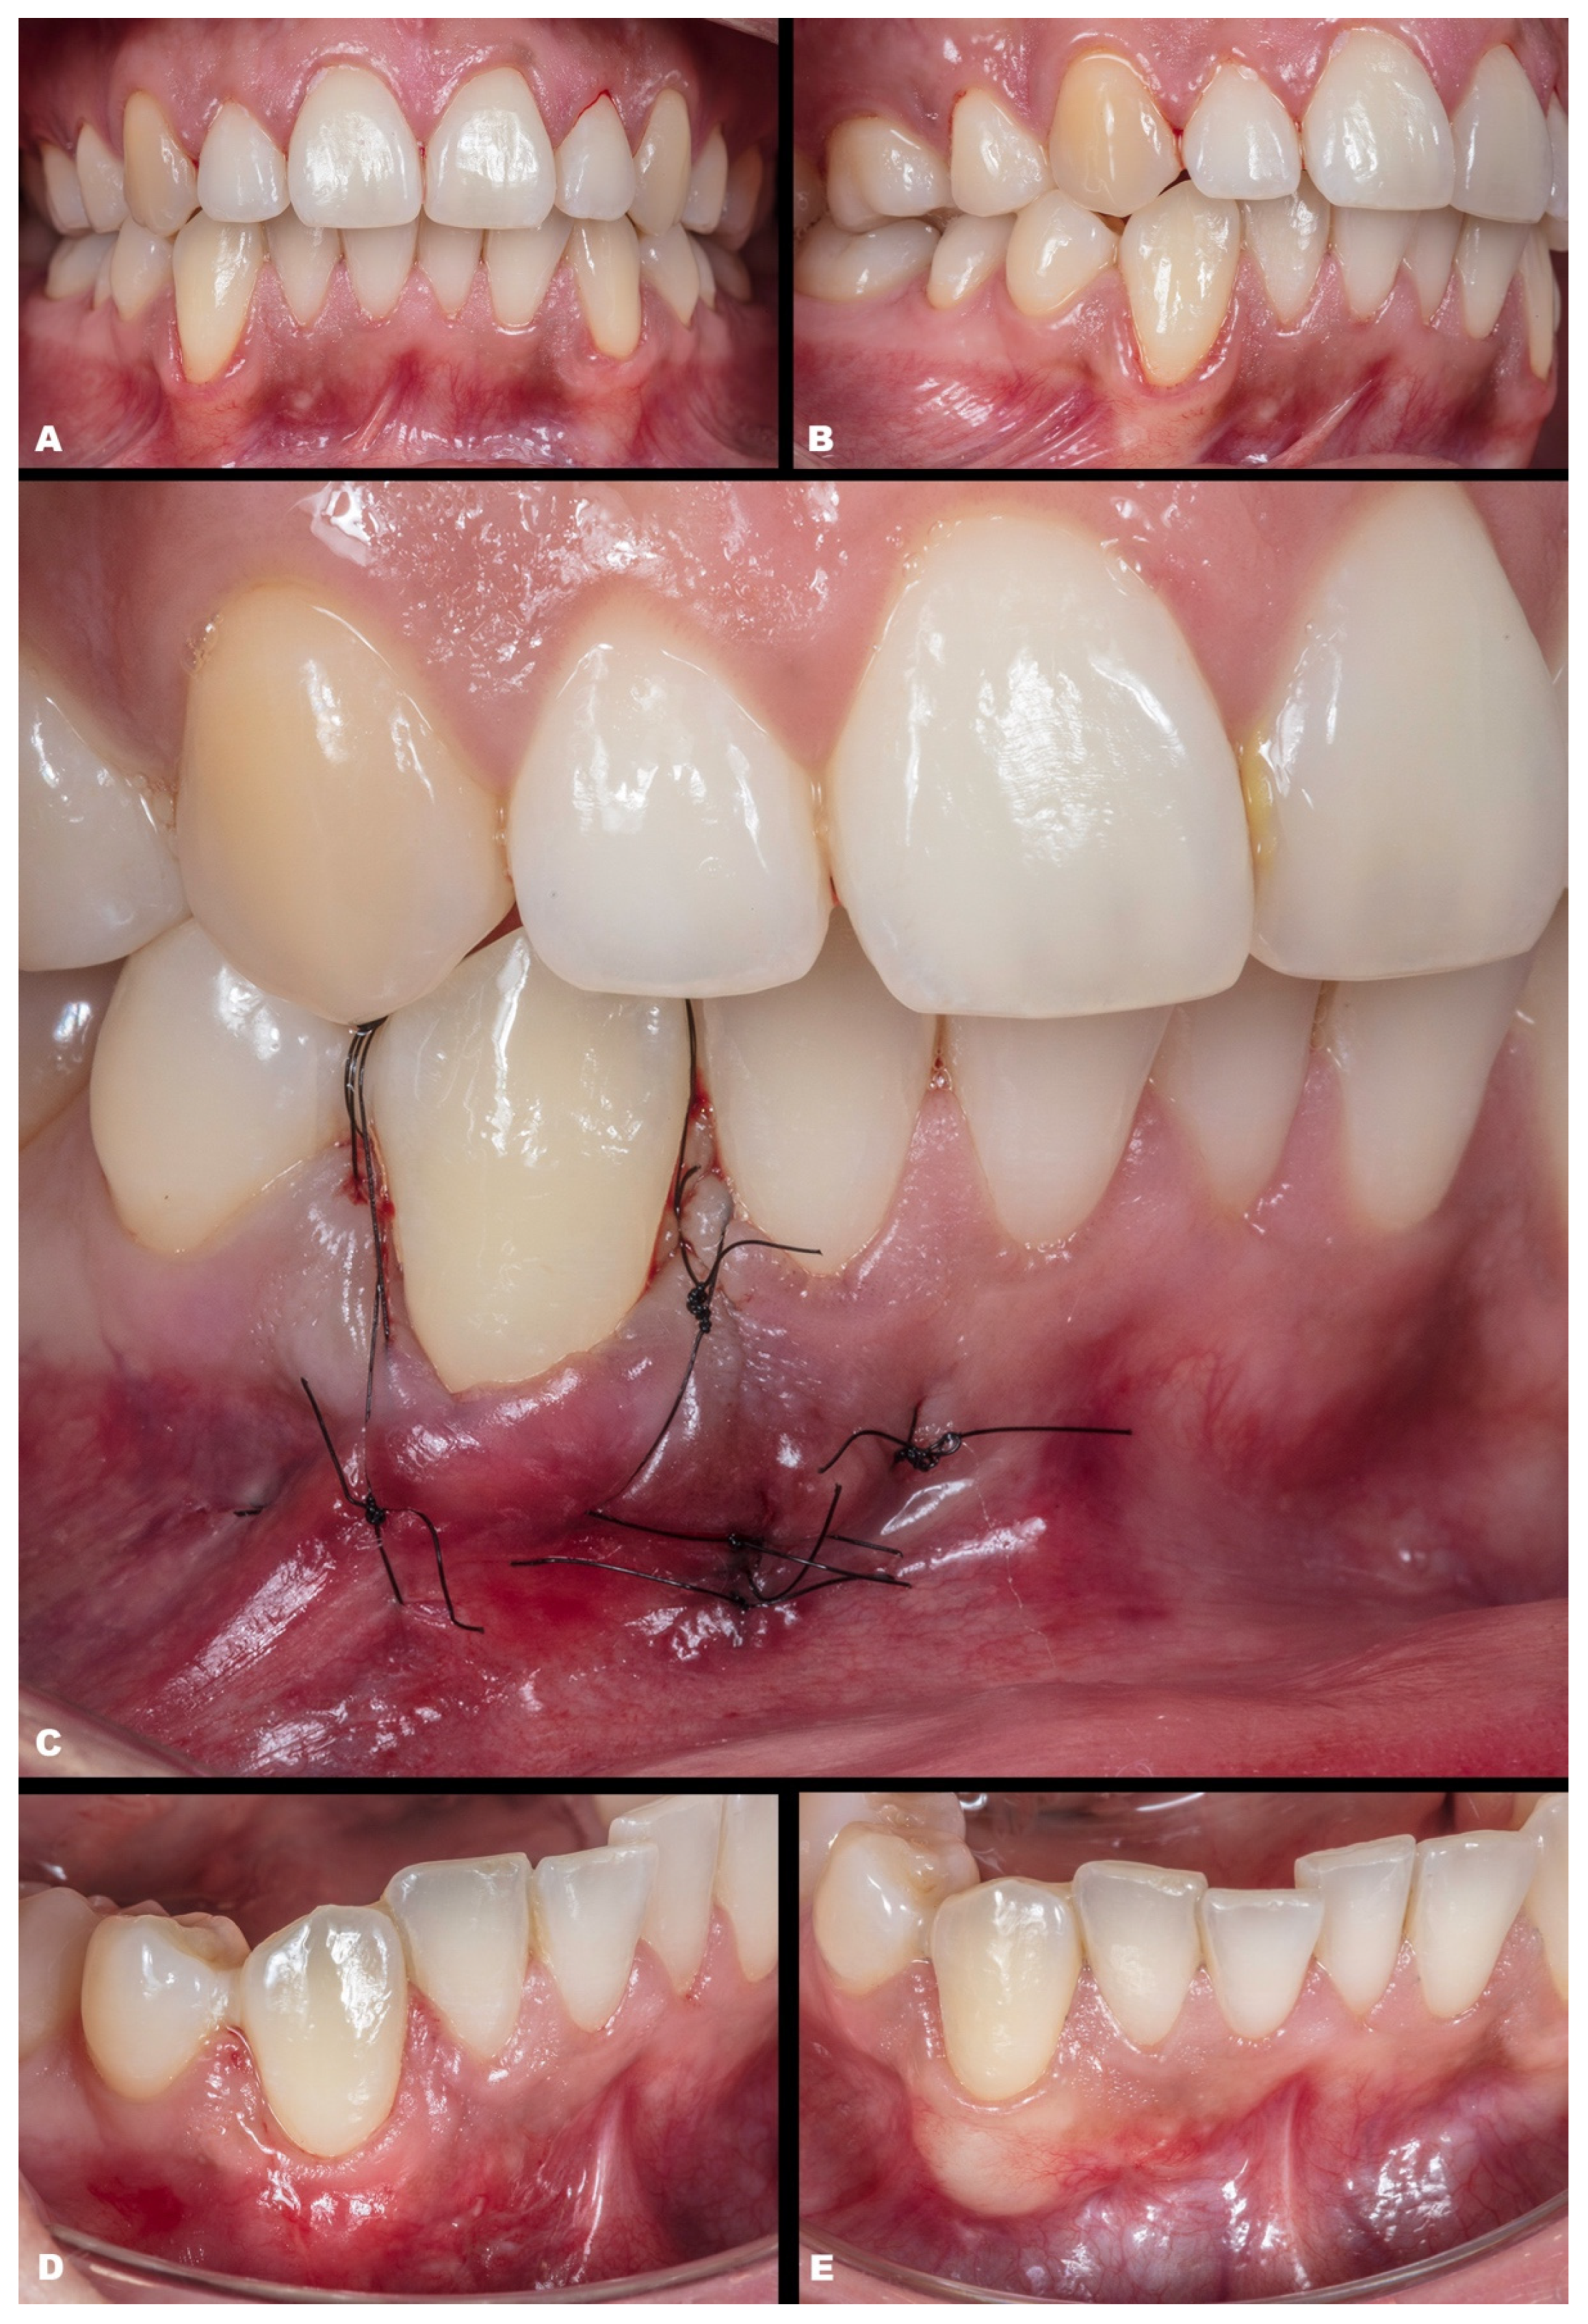

- (1)

- Vertical incision on the mucosa (around 1–2 mm apical to the MGJ), lateral to the papilla base (Figure 1D). It is mandatory not to perform this incision in the center of the papilla’s base, which might damage any vascular supply or risk damage to the papilla. In multiple recessions, it is recommended to perform two vertical incisions; and if extremely necessary, more vertical incisions can be performed, always in mucosa and lateral in the papilla’s base.

- (4)

- From the MGJ, subperiosteal access to raise the full-thickness tunnel is performed (Figure 1I), involving one adjacent tooth, to keep the local vascularization. The access is subperiosteal, and it is essential to act gently in this stage.

- (5)

- Confirm the tissue detachment until the gingival sulcus area (free gingival margin) and also in the papilla’s base (Figure 1J), keeping the papilla’s tip intact.

- (6)

- After CTG is harvested (either subepithelial or de-epithelialized), it will be inserted in the desired site through the linear incision or intrasulcularly (Figure 1K,L).

- (7)

- The CTG will be adjusted to cover the recession (Figure 1l) and must be coronally advanced at least 1 mm coronal to the CEJ.

- (8)

- Then, MiTT should be sutured according to the personally preferred technique. It is suggested that the suture techniques slightly pull the tunnel coronal (anchored with composite or double-crossed suture [18]). The vertical incision must be sutured with one or two single sutures. It is suggested to stabilize the soft tissues using interrupted sutures, and it may be used as adjunctive material, such as a biological glue. It is suggested that the suture be removed between 7 and 14 days.

| Classification | Gender | Tooth/Teeth with REC | Initial REC Height (mm) | Initial REC Width (mm) | Initial PD (mm) | Initial KTW (mm) | Final REC Height (mm) | Final PD (mm) | Final KTW (mm) | % RC | p-Value | |

|---|---|---|---|---|---|---|---|---|---|---|---|---|

| Baseline | 6-Month Follow-up | |||||||||||

| Case 9 | RT1 | F | 12 13 | 1.3 2.1 | 2.2 2.3 | 1.5 2.0 | 4.4 5.3 | none | 2.5 1.5 | 4.6 5.2 | 100 100 | |